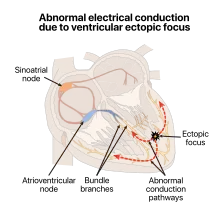

.svg.png) | |

| Premature ventricular contraction usually originates from an area of Ectopic focus. In this illustration ectopic area is near papillary muscles in the left ventricle. Most commonly in healthy hearts PVCs occur near right ventricular outflow tract (RVOT). | |

Normally, impulses pass through both ventricles almost at the same time and the depolarization waves of the two ventricles partially cancel each other out in the ECG. However, when a PVC occurs the impulse nearly always travels through only one bundle fiber, so there is no neutralization effect; this results in the high voltage QRS wave in the electrocardiograph.

There are three main physiological explanations for premature ventricular contractions: enhanced ectopic nodal automaticity, re-entry signaling, and toxic/reperfusion triggered.

Ectopic enhanced nodal automaticity suggests foci of sub-pulmonic valvular pacemaker cells that have a subthreshold potential for firing. The basic rhythm of the heart raises these cells to threshold, which precipitates an ectopic beat. This process is the underlying mechanism for arrhythmias due to excess catecholamines and some electrolyte deficiencies, particularly low blood potassium, known as hypokalemia.

Reentry occurs when an area of 1-way block in the Purkinje fibers and a second area of slow conduction are present. This condition is frequently seen in patients with underlying heart disease that creates areas of differential conduction and recovery due to myocardial scarring or ischemia. During ventricular activation, one bundle tract's area of slow conduction activates the other tract's bundle fibers post block after the rest of the ventricle has recovered. This resulting in an extra beat. Reentry can produce single ectopic beats, or it can trigger paroxysmal tachycardia.

This ectopy of the ventricles when associated with a structurally normal heart most commonly occurs from the right ventricular outflow tract (RVOT) under the pulmonic valve. The mechanism behind this is thought to be enhanced automaticity versus triggered activity.[3]